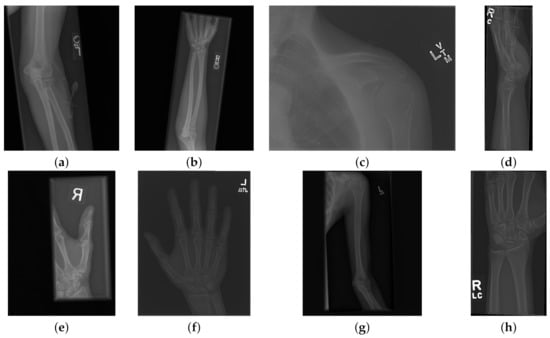

For the 11 architectures with no data augmentation, Inception-Resnet-v2 performs the best with an accuracy ( A c = 0.723 ) and Cohen’s kappa ( κ = 0.506 ). DenseNet-201 fares slightly lower ( A c = 0.717 , κ = 0.497 ). The lowest results were obtained with GoogleNet ( A c = 0.654 , κ = 0.381 ). This potentially indicates better feature extraction with deeper network architectures. Figure 5 and Figure 6 illustrate some cases of the classification for Lateral and Postero-anterior views of wrist radiographs.

Figure 5. Illustration of classification results for lateral (LA) views of wrist radiographs. (a) Corresponds to positive (abnormal) diagnosis image but predicted as negative (normal), (b) Abnormal diagnosis and abnormal prediction. (c) Normal diagnosis image and normal prediction. (d) Normal diagnosis and abnormal prediction. Notice that the errors in classification may have been biased by artefact elements on the images.

Figure 6. Illustration of classification results for postero-anterior (PA) views of wrist radiographs. (a) corresponds to a positive (abnormal) diagnosis image that is predicted as negative (normal); (b) to abnormal diagnosis and abnormal prediction; (c) to normal diagnosis image and normal prediction; and (d) to normal diagnosis and abnormal prediction. Notice again that the errors in classification may have been biased by artefactual elements on the images.